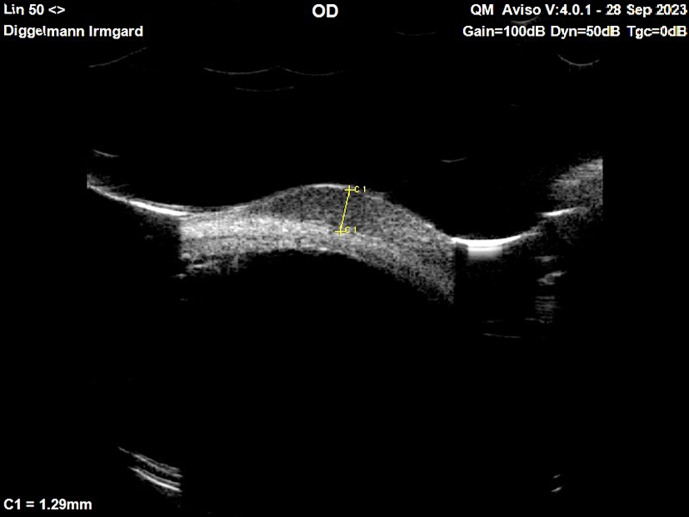

Introduction: Conjunctival melanoma (CM) is a rare but potentially lethal ocular malignancy that arises from melanocytes in the conjunctiva. Its clinical presentation can mimic other more common conjunctival lesions, such as squamous cell carcinoma (SCC), leading to diagnostic challenges.

Case presentation: We present a case of CM initially misdiagnosed as conjunctival SCC due to overlapping clinical features.

Conclusion: CM presenting as nonpigmented, conjunctival tumor is a diagnostic challenge. Clinicians should maintain a high index of suspicion for conjunctival melanocytic or amelanotic lesions, particularly those with atypical features.